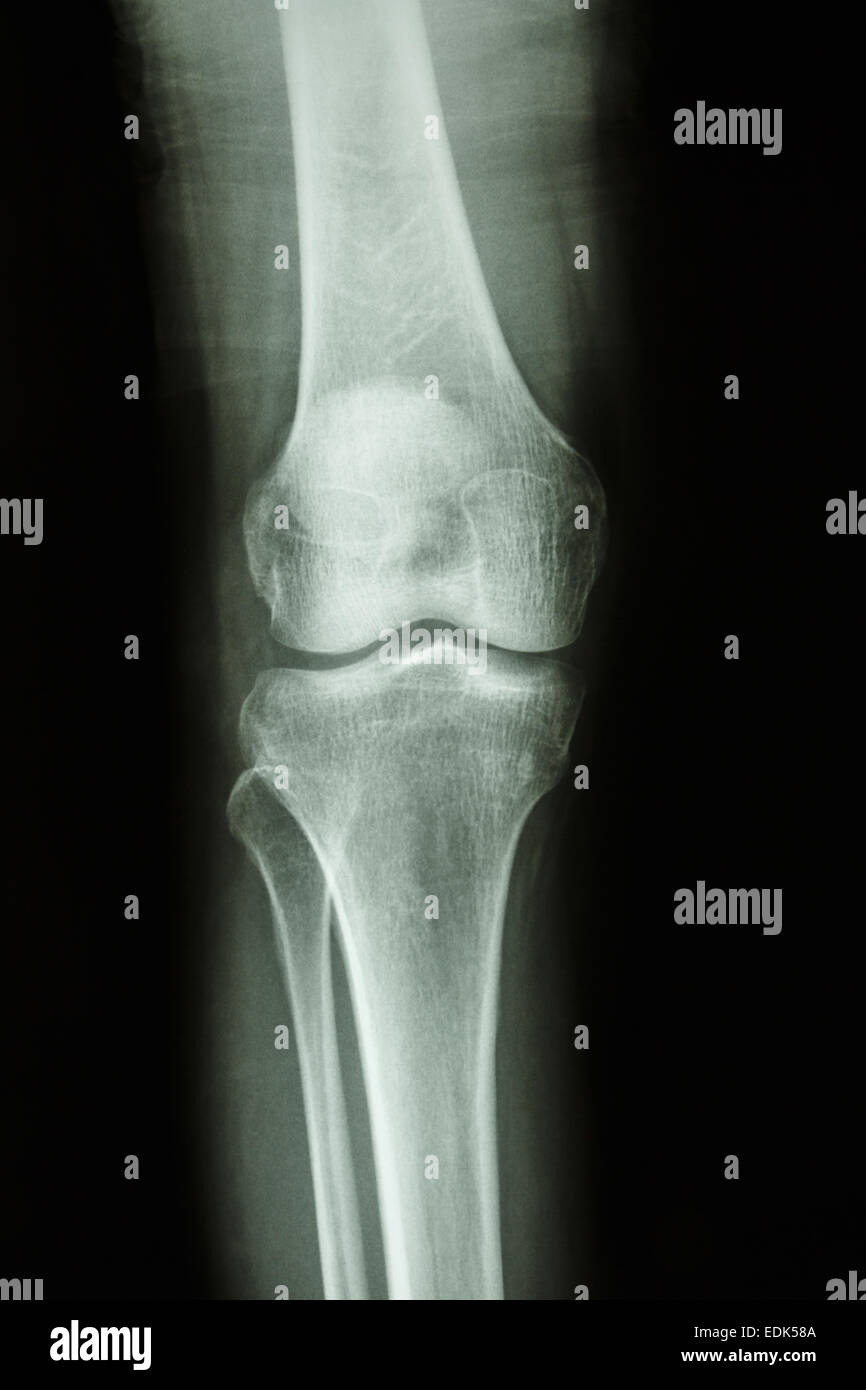

Flim X-ray genou AP : montrer l'articulation du genou humain normal Banque D'Imageshttps://www.alamyimages.fr/image-license-details/?v=1https://www.alamyimages.fr/photo-image-flim-x-ray-genou-ap-montrer-l-articulation-du-genou-humain-normal-77253242.html

Flim X-ray genou AP : montrer l'articulation du genou humain normal Banque D'Imageshttps://www.alamyimages.fr/image-license-details/?v=1https://www.alamyimages.fr/photo-image-flim-x-ray-genou-ap-montrer-l-articulation-du-genou-humain-normal-77253242.htmlRFEDK58A–Flim X-ray genou AP : montrer l'articulation du genou humain normal